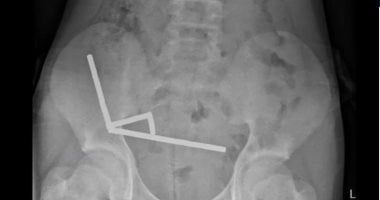

أعلن مستشفى تورانغا في الجزيرة الشمالية عن حالة صبي مراهق يبلغ من العمر 13 عامًا أُحضِر إلى المستشفى وهو يعاني من آلام في البطن استمرت أربعة أيام. وأظهرت الأشعة وجود ما يقارب 80 إلى 100 مغناطيس نيوديميوم عالي القدرة، مقاس 5×2 ملم، داخل الأمعاء. وأضاف التقرير أن المغناطيسات كانت قد حُظرت في نيوزيلندا منذ يناير 2013 وتم شراؤها من منصة تسوق عبر الإنترنت. وأظهرت الصورة أن المغناطيسات تشكلت في أربعة خطوط مستقيمة داخل الأمعاء وتلاصقت بفعل القوة المغناطيسية.

أوضح أطباء المستشفى في المجلة الطبية النيوزيلندية أن ضغط المغناطيسات تسبب في نخر في أربع مناطق من الأمعاء الدقيقة والأعور، فجرى إجراء جراحة لإزالة الأنسجة الميتة واستعادة المغناطيسات. عاد الطفل إلى المنزل بعد ثمانية أيام من الرعاية في المستشفى. وذكر التقرير أن الفتى كان قد اشتراها عبر منصة تسوق على الإنترنت. أظهرت الأشعة أن المغناطيسات كانت مرتبة في أربعة خطوط مستقيمة داخل الأمعاء.